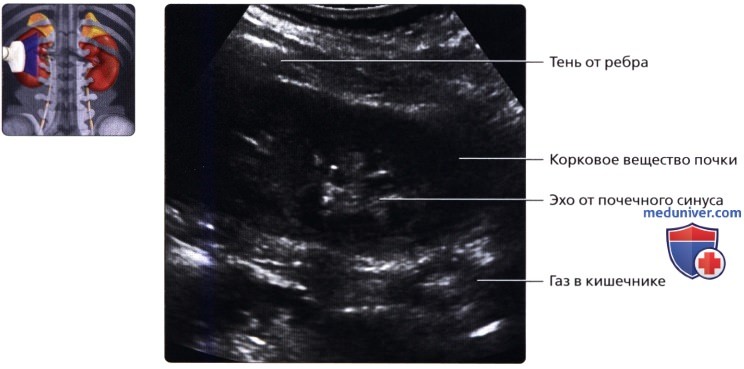

б) Лучевая анатомия почки:

• Забрюшинные структуры бобовидной формы с четким контуром, смещающиеся при дыхании

в) Особенности визуализации почек:

1. Рекомендации по визуализации:

• Правая почка:

о Печень используется в качестве акустического окна

о Датчик устанавливается в подреберье или в межреберный промежуток

о Выполняйте исследование при различной глубине вдохе

о Попросите пациента немного повернуться влево, приподняв правый бок и выполняйте сканирование с боковой/заднебоковой поверхности

— Качество изображения может снижаться из-за теней от околопозвоночных мышц и ребер